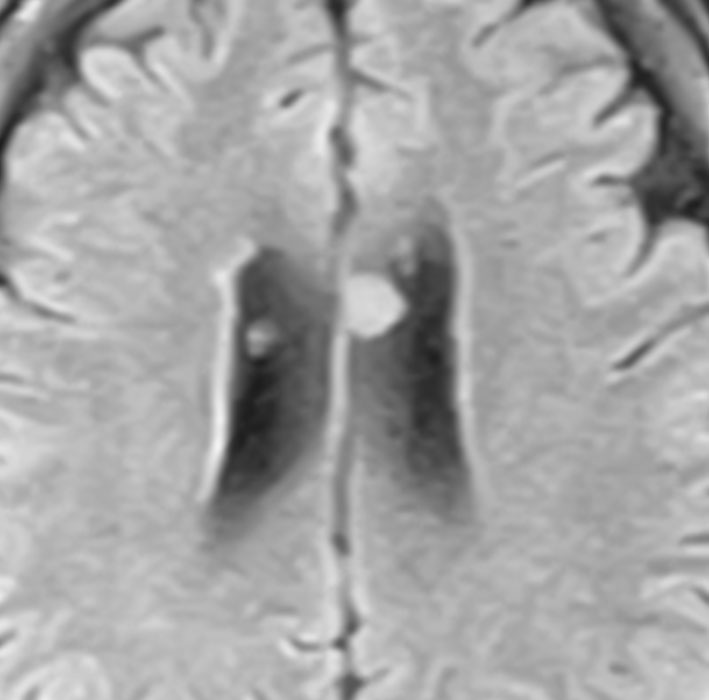

45歳で偶然に発見されたものです。上衣下腫の多発例というより,T1は等信号でガドリニウム増強されません。軽症の結節性硬化症 tubrous sclerosis にみられる多発性上衣下結節 と診断したほうがいいでしょう。